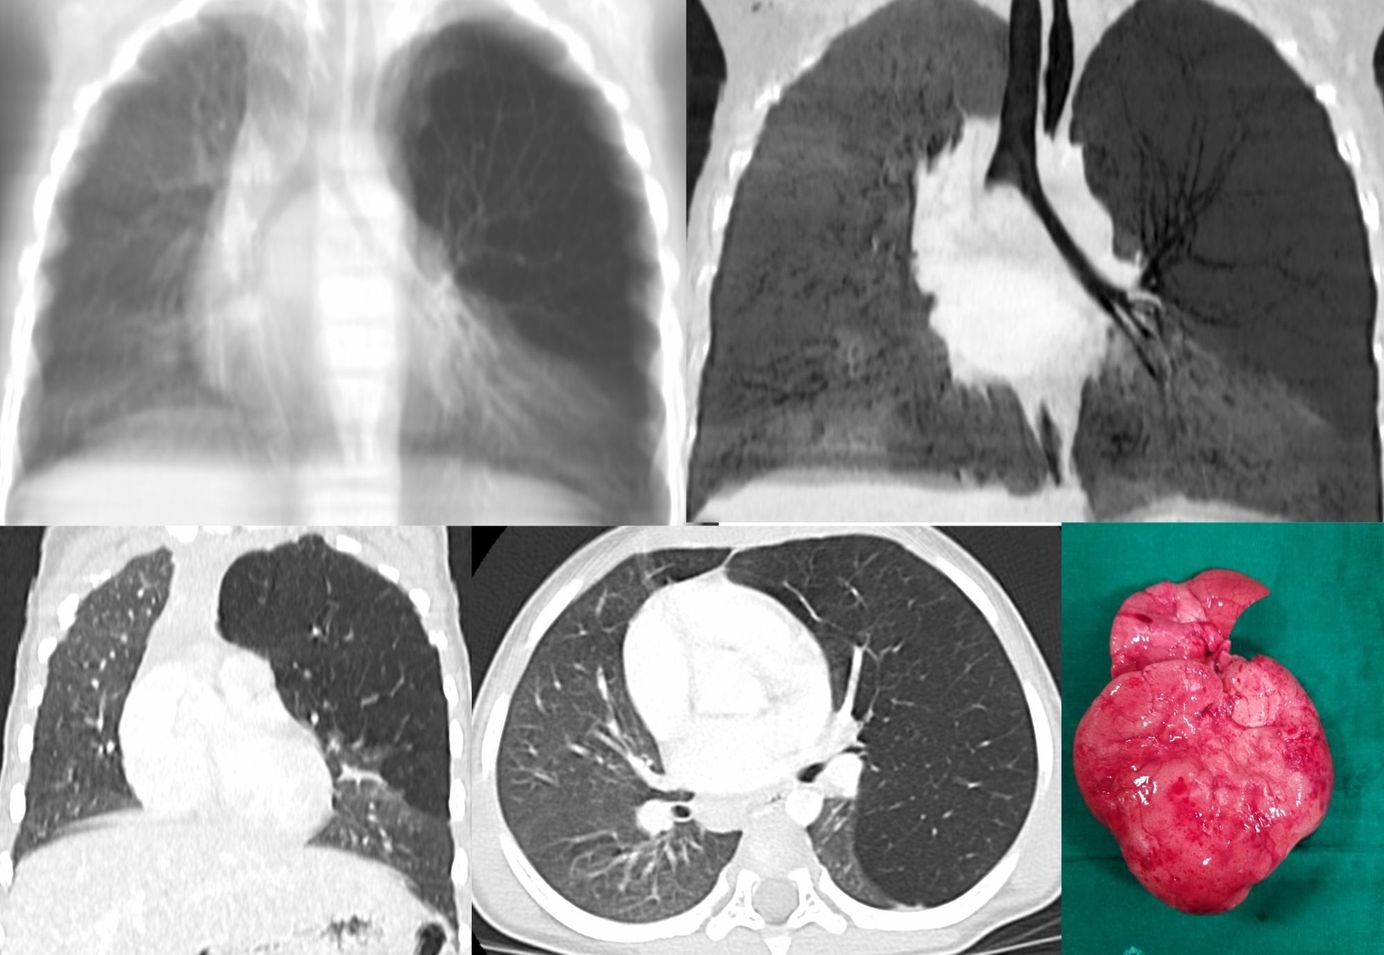

Case 17: Tuberculosis and Hemoptysis - Dense and Soft Centrilobular Nodules Together Members Public

17-years old with tuberculosis and hemoptysis - dense and soft centrilobular nodules together.